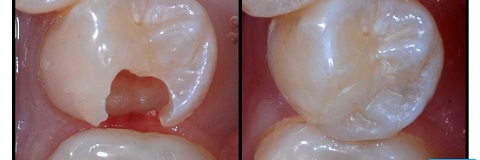

Răng cửa bị mẻ có trám được không? Trường hợp răng cửa bị sứt mẻ, gãy vỡ do chấn thương, ăn thức ăn quá cứng, thói quen nghiến răng/mở đồ bằng răng, … thì trám răng là giải pháp hiệu quả. Bạn nên thực hiện trám răng cửa bị mẻ sớm, nhằm ngăn ngừa tình trạng viêm nhiễm, giảm nguy cơ răng bị sứt mẻ nặng hơn khi ăn nhai.

Trám răng cửa bị mẻ sứt là giải pháp cải thiện thẩm mỹ, ngăn ngừa tình trạng răng bị mẻ, gãy nghiêm trọng hơn.

Trám răng cửa là phương pháp ít xâm lấn, bảo tồn tối đa răng cửa bị sâu được nhiều bác sĩ chỉ định. Phương pháp này giúp bịt kín lại các lỗ sâu, ngăn ngừa sự lây lan của vi khuẩn.

Trong trường hợp răng mới chớm sâu hoặc lỗ sâu đã hình thành nhưng chưa bị vỡ, mẻ quá nhiều, bác sĩ tư vấn thực hiện trám răng cửa, giúp ngăn ngừa vi khuẩn lây lan.